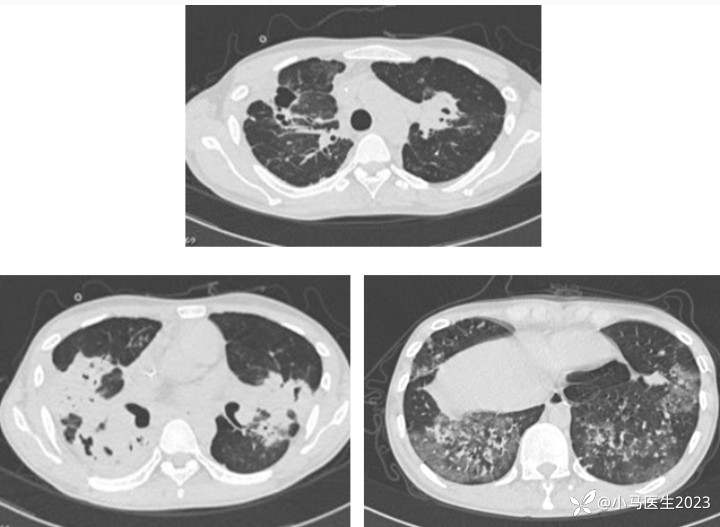

胸部CT表现

吸入/淋巴道传播

下肺分布优势

累及双肺,多叶段分布

实变、磨玻璃、粟粒细节、网格结节等

胸膜增厚,胸腔积液

与结核极易混淆!